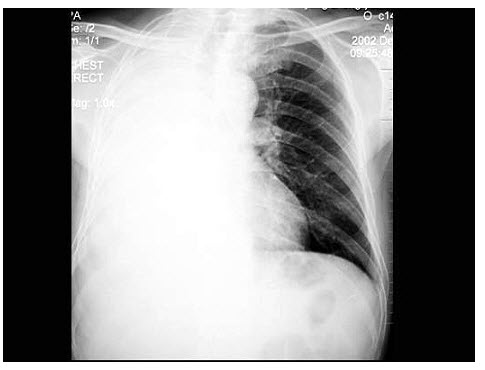

15、单项选择题

男,27岁,近2月来感胸闷,无咳嗽咳痰,不发热,X线检查如图,最可能的诊断是()

男,20岁,胸闷、低热1月余,突然咯血,X线检查如图,最可能的诊断是()

A.肺结核(Ⅰ型)伴右侧胸腔积液

B.肺结核(Ⅲ型)伴右侧胸腔积液

C.肺结核(Ⅱ型)伴右侧肺不张

D.肺结核(Ⅲ型)伴右侧肺不张

E.肺转移瘤伴右侧肺不张